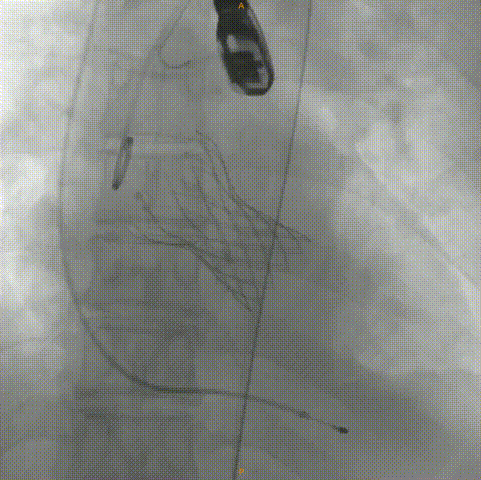

主动脉根部造影

输送器顺利过弓、跨瓣

瓣膜标准位定位

瓣膜释放到工作位

工作位造影

位置理想,瓣膜完全释放

释放后造影